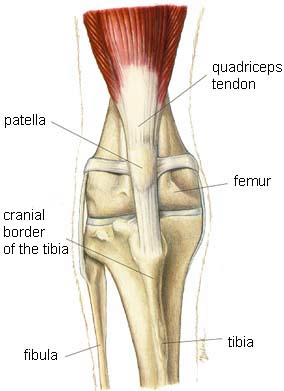

The musculoskeletal system includes all the muscles, bones and joints.

- Stifle (knee)

Stifle (knee)